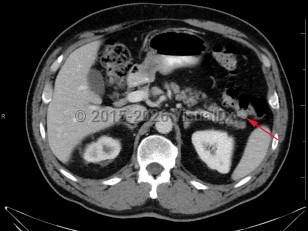

Anemia, Seizure, 50-59 year old Female